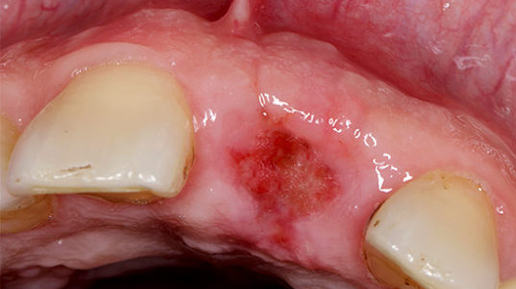

[Лунка после удаления зуба] требует особо внимательного отношения и ухода, ведь данная процедура – полноценная операция, после которой организму нужен период восстановления. В это время запускаются регенерационные процессы, и ранка должна быстро зажить самостоятельно. Человеку требуется лишь соблюдать несколько дней тщательный, но бережный уход. Необходимо следить за процессом восстановления, чтобы в случае необходимости сразу же пойти к специалисту и предупредить возможные осложнения. Стадии...

Как заживает лунка после удаления зуба?

В норме ранка затягивается на 14—18 день после удаления зуба. Но еще примерно два месяца лунка продолжает зарастать молодой «рыхлой» костью. На третьем-четвертом месяце кость уплотняется и приобретает обычное строение. Иногда в лунке развивается воспалительный процесс. В этом случае заживление занимает больше времени. Лунка заживает в несколько этапов: Сразу после удаления зуба кровь в ранке сворачивается и образует кровяной сгусток. Он защищает рану от микробов, а еще способствует ее дальнейшей регенерации...